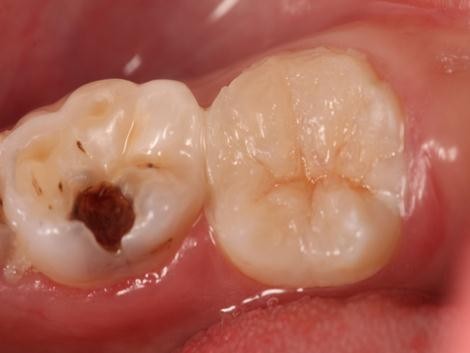

树脂修复病例

患者,女,右下6龋坏要求修复,平素体质一般,无药物、食物过敏史,无高血压、心脏病等系统病史。

去腐,树脂修复